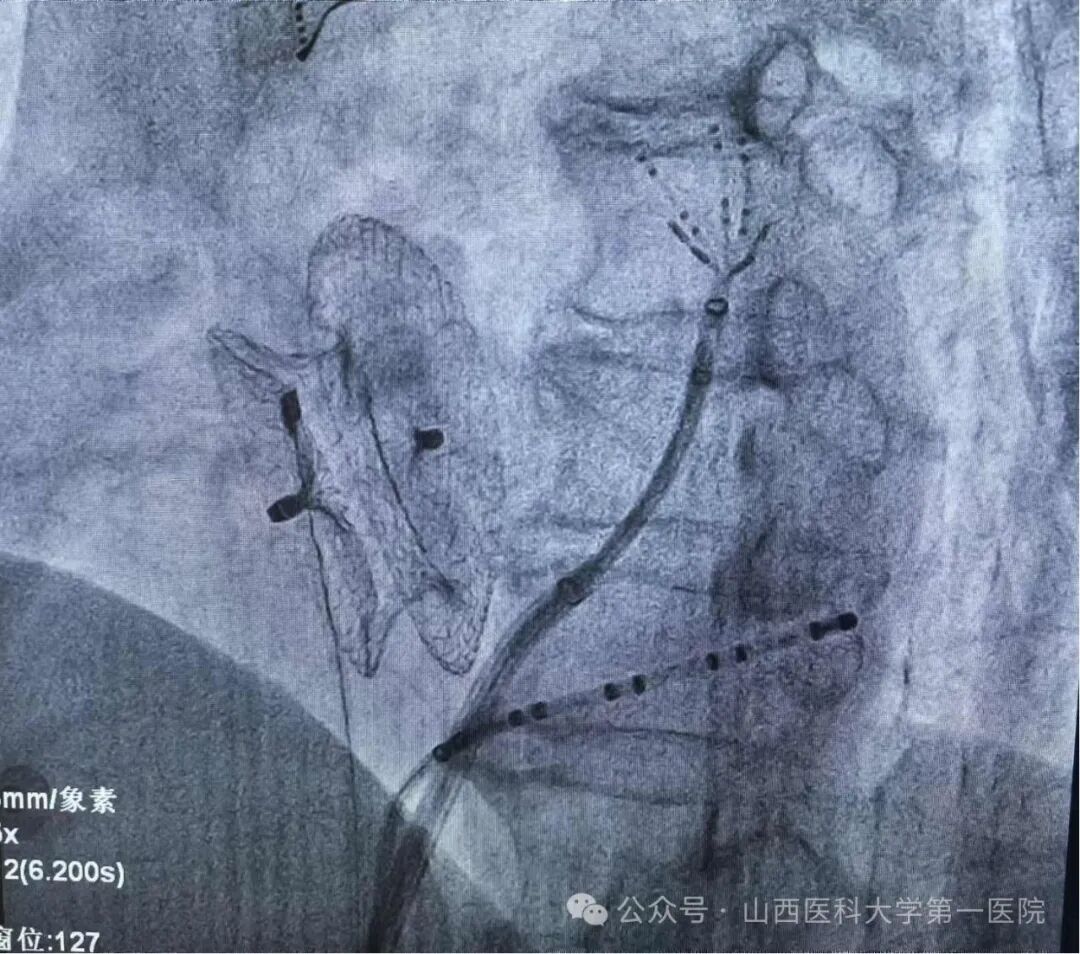

患者术中影像图

双心房标测证实局灶靶点,经消融成功终止房扑